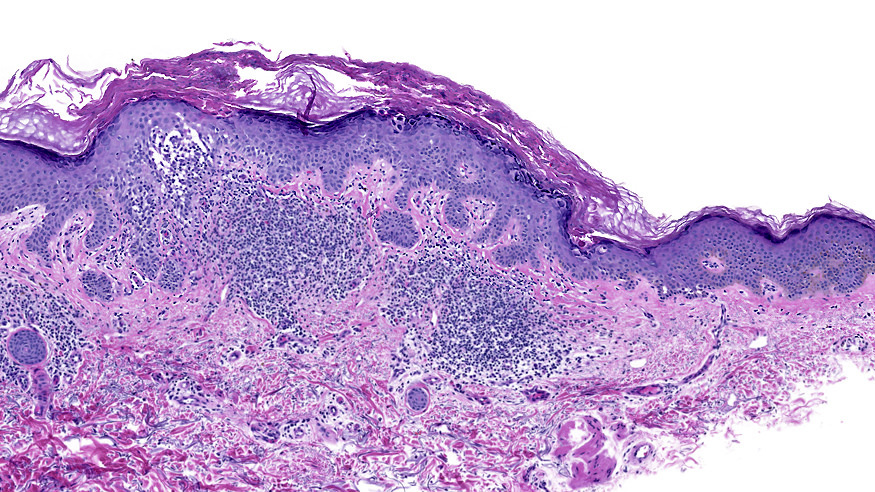

Microscopic (histologic) description

- Suprabasal acantholysis with vesicle formation is the principal microscopic finding

- Main 4 histopathological patterns are:

- Hailey-Hailey-like: suprabasal acantholysis of all levels of the epidermis without significant dyskeratosis (dilapidated brick wall appearance)

- More than one pattern can be seen in the same setting

Microscopic (histologic) images